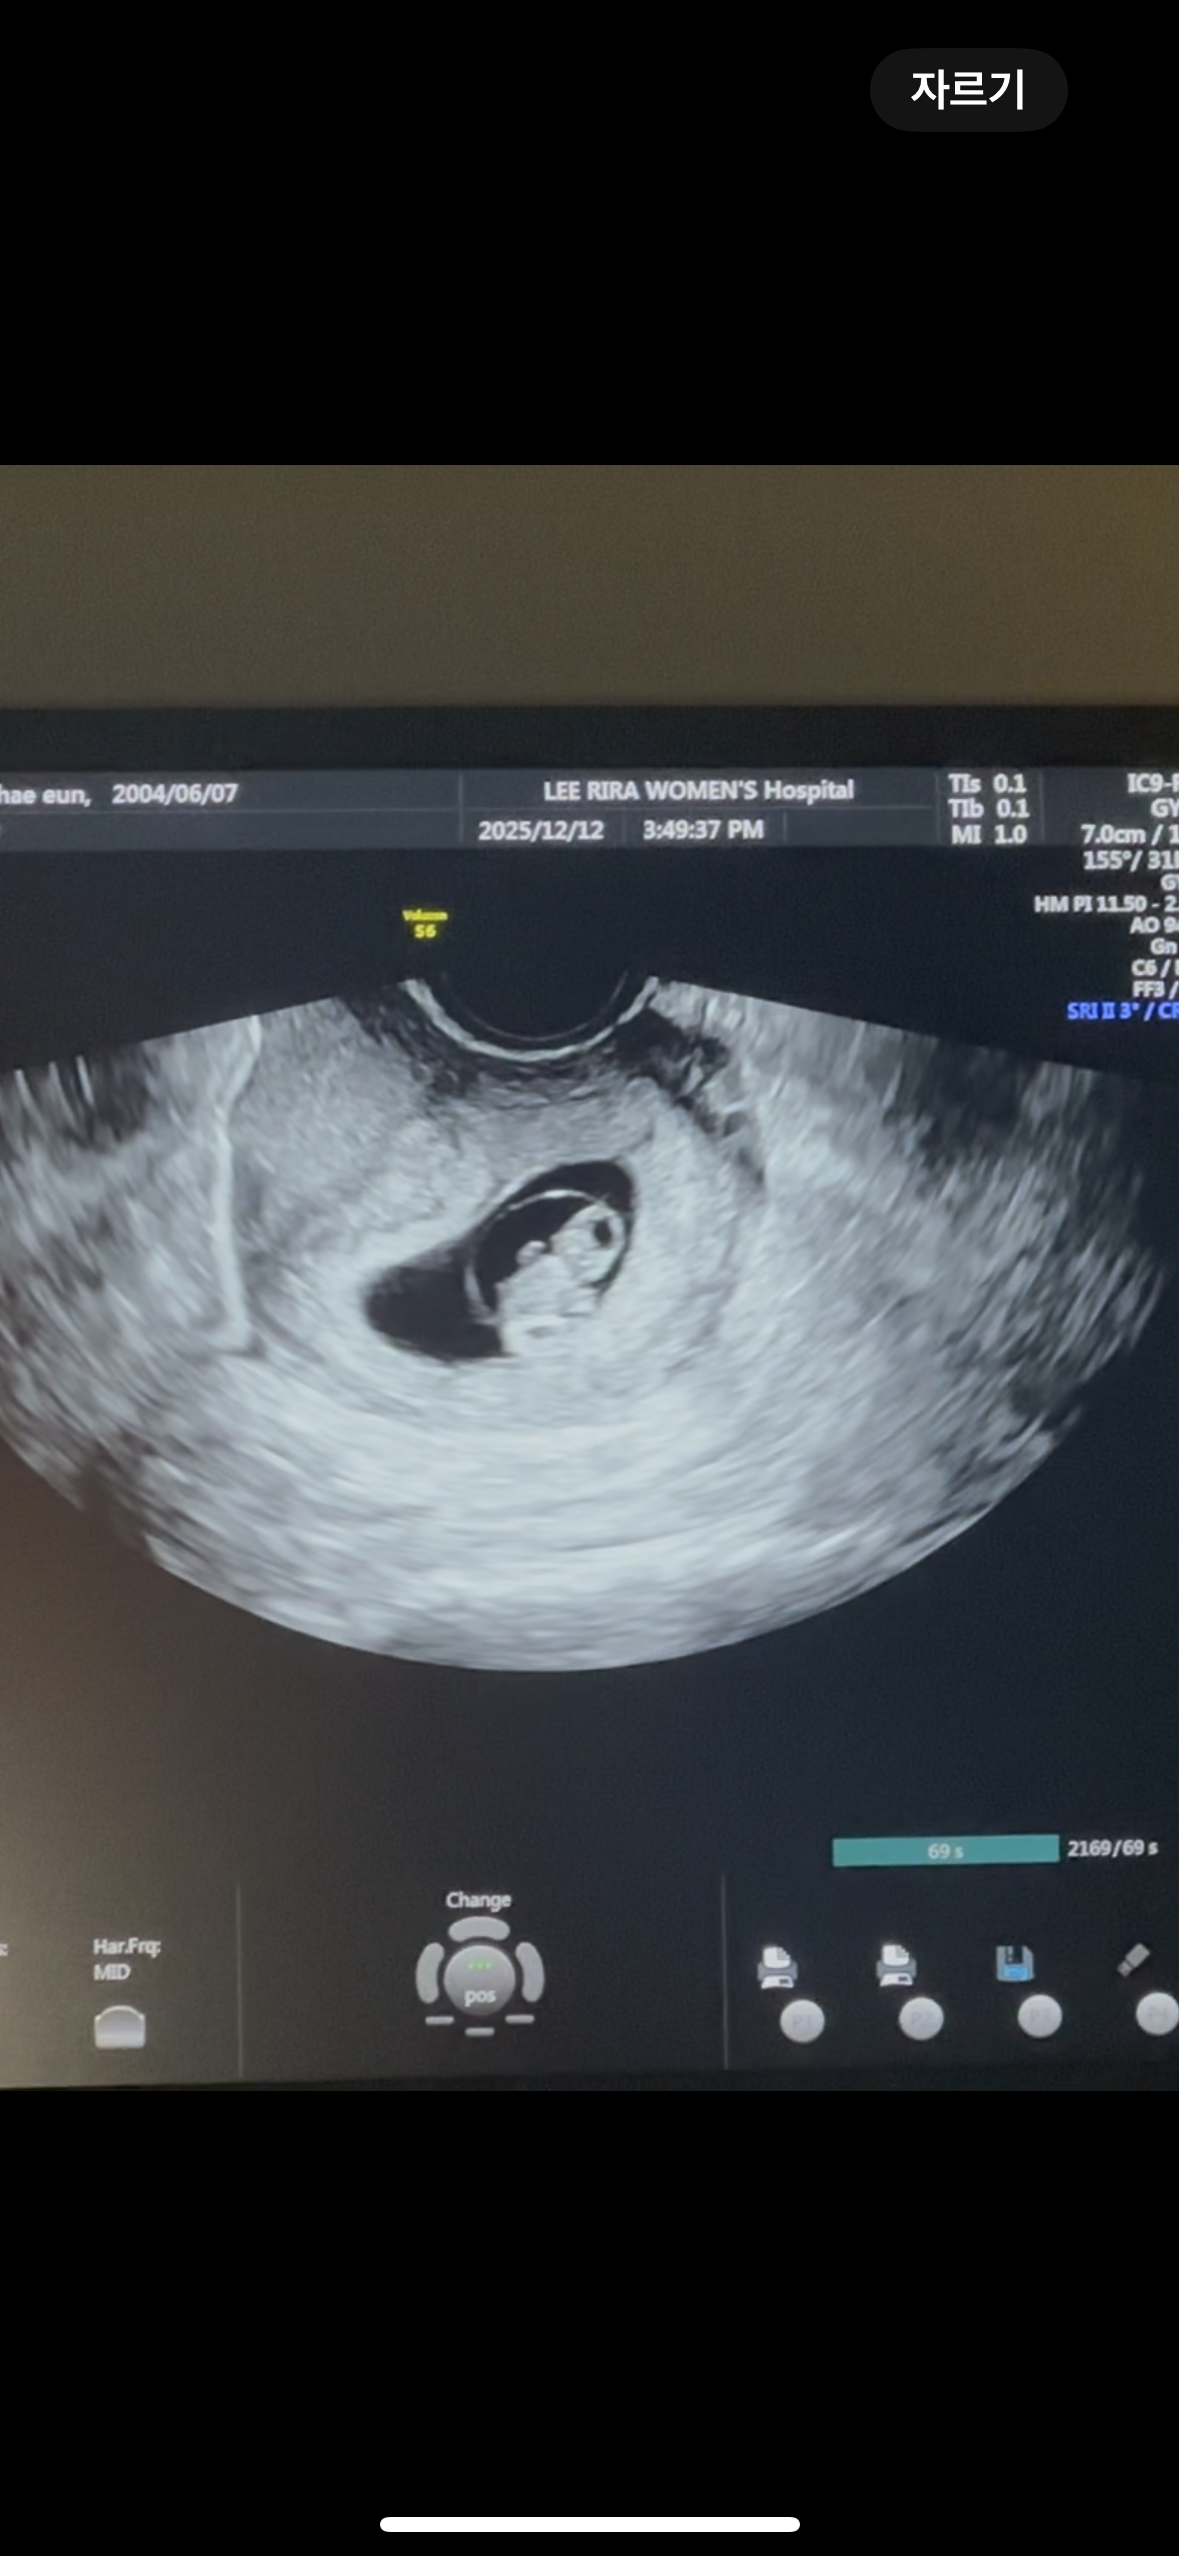

8주차때 초음파인데 딸일까요 아들일까요

성별이 어떻게 될까용 너무 궁금해용 ㅎㅎ!! 아들일까요 딸일까용~~!!!